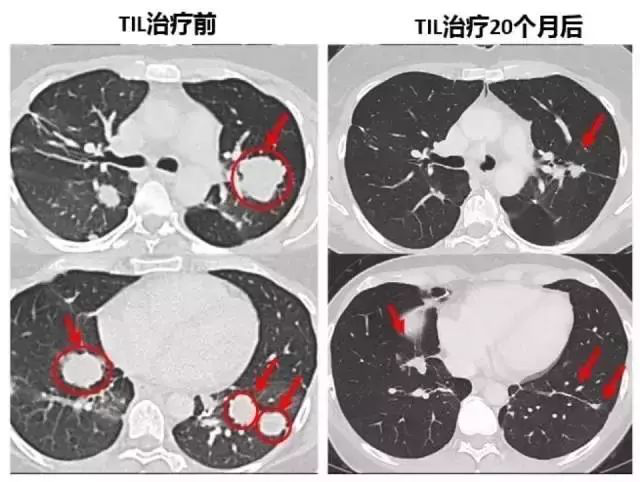

22個(gè)月后,這名患者的腫瘤(黃色箭頭)消失得無影無蹤(圖片來源:《Nature Medicine》)

轉(zhuǎn)移性結(jié)直腸癌患者腫瘤患者經(jīng)過TIL細(xì)胞療法治療后,7個(gè)肺部的轉(zhuǎn)移灶在幾周后都變小乃至消失!